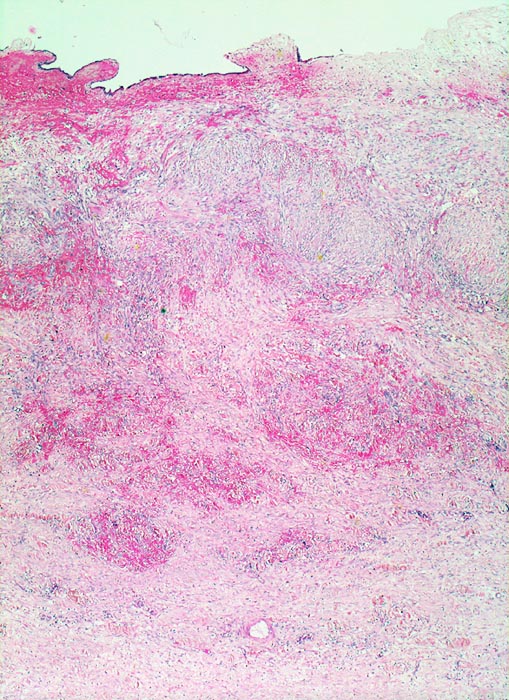

PathoPic ID 3416 - chronische fibroplastische Cholezystitis bei Cholezystolithiasis

chronische fibroplastische Cholezystitis bei Cholezystolithiasis

Entzündung / Reparatur

Gallenblase

Leber, Gallenwege, Pankreas

Das Schleimhautrelief ist abgeflacht. Die Gallenblasenwand ist stark fibrosiert und hämorrhagisch.

Wiederholte rechtsseitige Oberbauchbeschwerden.

Histologie

25